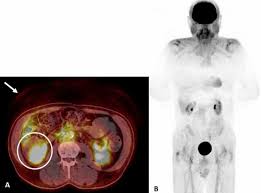

F-Conal FDG PET Scan in Delhi